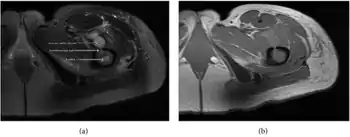

| a,b) MRI showing the Brodie's abscess in the left proximal femur | |

Axial T1-weighted MRI pre-contrast enhancement showing that the intramedullary collection is T1-hyperintense suggesting proteinaceous viscous fluid consistent with infection.

Axial T1-weighted fat-saturated MRI image following IV gadolinium contrast demonstrating the intramedullary lytic area seen on radiography to be ring enhancing consistent with a purulent fluid collection. Extensive circumferential periosteal enhancement is noted. There is also substantial bone marrow enhancement.